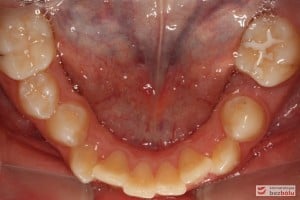

Rodzice zgłosili się z pacjentem celem rutynowej kontroli ortodontycznej. Wykonano OPG i po analizie modeli diagnostycznych stwierdzono brak miejsca dla wyrzynania dolnej prawej piątki stałej oraz zwężenie szczęki wraz z rotacją górnych zębów szóstych. W łuku górnym w pierwszym etapie leczenia zastosowano Rotator, celem odrotowania 6-tek stałych oraz ekspansji łuku w wymiarze poprzecznym. Następnie zamontowano aparat stały metalowy do uszeregowania zębów w łuku. W łuku dolnym miejsce odtwarzano stosując aparat stały i odpowiednią mechanikę leczenia. Leczenie aktywne trwało 3,5 roku, po czym zastosowano terapię retencyjną (retainer stały w żuchwie oraz Płytkę Hawley’a w szczęce).